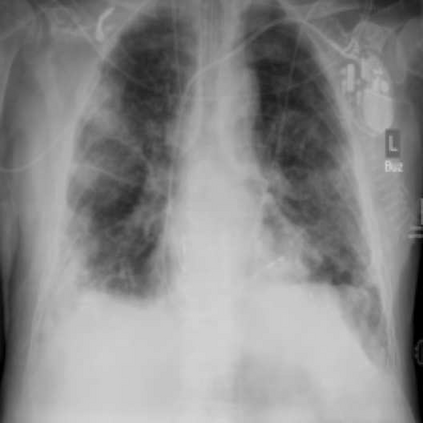

Since the beginning of the COVID-19 pandemic, researchers have developed deep learning models to classify COVID-19 induced pneumonia. As with many medical imaging tasks, the quality and quantity of the available data is often limited. In this work we train a deep learning model on publicly available COVID-19 image data and evaluate the model on local hospital chest X-ray data. The data has been reviewed and labeled by two radiologists to ensure a high quality estimation of the generalization capabilities of the model. Furthermore, we are using a Generative Adversarial Network to generate synthetic X-ray images based on this data. Our results show that using those synthetic images for data augmentation can improve the model's performance significantly. This can be a promising approach for many sparse data domains.